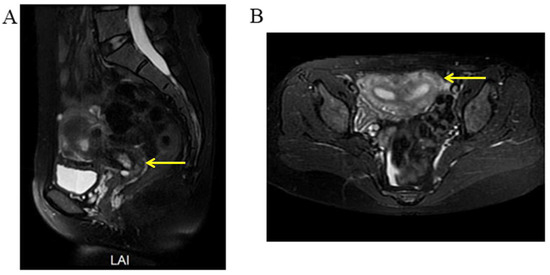

2.5. Case 5

A woman of 33 years old was advised to undergo a hysteroscopy before receiving assisted reproductive technologies. She received a hysteroscopic uterine septum resection at age 27. Her right fallopian tube was removed due to two ectopic pregnancies. A pelvic examination showed an oblique septum extending 3 cm from the left fornix of the vagina to the hymen border. The pelvic ultrasound demonstrated an ectopic ureter or ureterovaginal fistula (Figure 10). An MRI and CTU detected left renal agenesis and a left dilated ureter with an ectopic opening. Following vaginal septum excision, a double cervix with a dysplastic left cervix was found. Given that the left ectopic ureter was asymptomatic, this ectopic ureter was not surgically removed.

Figure 10.

The pelvic ultrasound demonstrated that a sausage-shaped ectopic ureter (yellow arrow) was found behind the uterus and bladder.